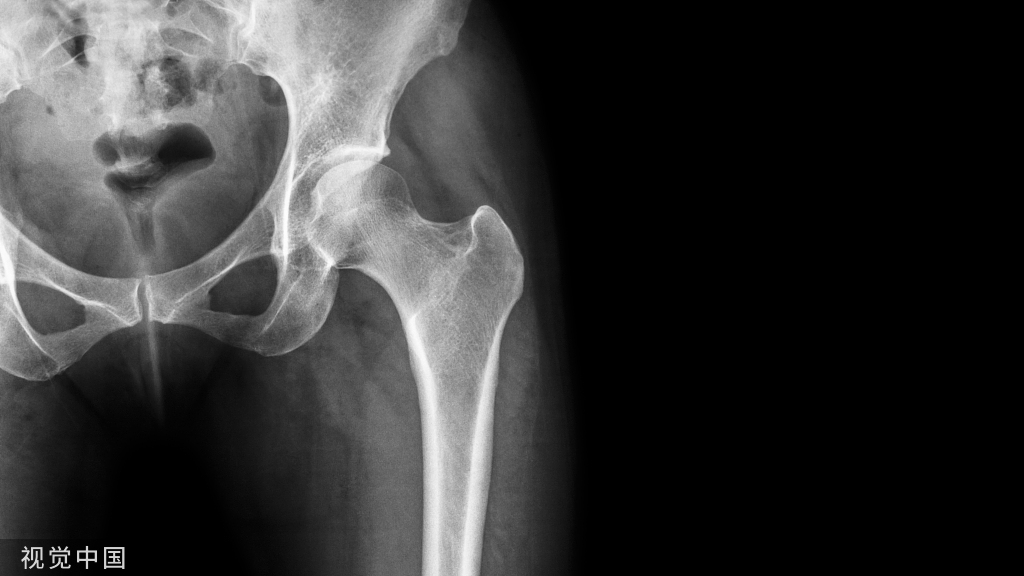

股骨干骨折复位固定的适应症,主要是股骨干部骨折,即指股骨小粗隆以下 2~5cm和 股骨髁上2~5cm的干部骨折。

由于大腿的解剖生理特点,股骨干为人体内最大的长管状骨,坚强而粗大,周围有强有力的肌群包绕。在股前区上部股三角内有股神经、股动脉、股静脉、腹股 沟下深、浅淋巴结及股深动、静脉等结构。股三角上界为腹股沟韧带,该韧带中心向下可触 及股动脉搏动。内界为长收肌内缘,外界为缝匠肌内缘。股三角的尖端距腹股沟韧带约 10cm,该区由于重要器官集居,故股三角区是穿针的禁区。

穿针经皮肤——缝匠肌前缘——股内侧肌——骨皮质其由皮肤至骨骼的深度最短4cm,最深5 8cm, 平均为5.2cm。自缝匠肌外缘穿针观察测量骨针与股动、静脉和隐神经之间的距离,最近者1.2cm,最远 者2cm,平 均 为1.7cm。说明骨针与大腿内侧重要血管和神经之间,有着 相当安全的距离。经临床医疗实践观察, 自缝匠肌前缘安垒线,经皮穿针,未发现任何穿针 并发症。

大腿穿针安全线的设计:1.股动脉的体表位置:自髂前上棘和耻骨结节连线中点,至大腿内侧中下1/3交界处的连线为股动脉体表标志。若沿此线继续向下, 自下1/3交界处至腘窝中点的连线,则为腘窝动脉体表标志。

2.安全线的测划:自髂前上棘和耻骨结节连线中外1/3交界点,与髌骨内缘与股骨内髁后缘连线的中点,此二点联线为穿针安全线, 基本相当于缝匠肌的走行。